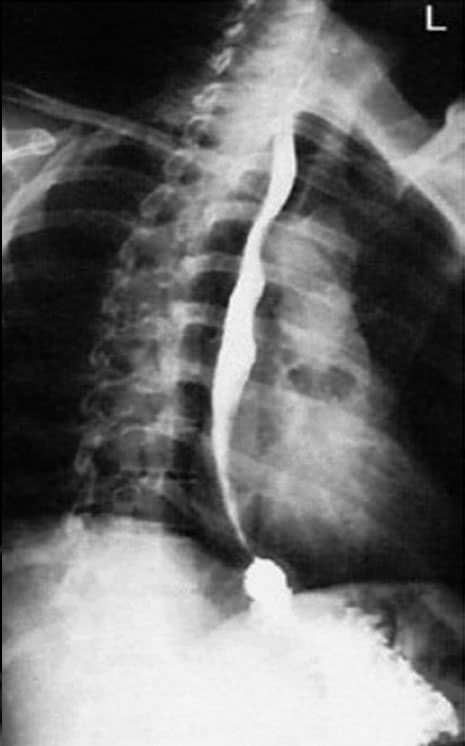

Radiografias do esôfago contrastado em OAD (à esquerda) e em perfil (à direita).

Justificativa para realização do exame

Encontrar estreitamentos e corpos estranhos; anomalias anatômicas e neoplasias do esôfago são demonstradas nessa incidência radiológica.

Principais estruturas demonstradas

Toda extensão do esôfago em perfil, sem a sobreposição da coluna torácica e da área cardíaca.

Fatores técnicos e posicionamento

• DFF: 1m.

• Tamanho do filme/receptor de imagem e sentido: 30x40cm no sentido longitudinal.

• Técnica de referência: 6mAs e 110KV, na mesa ou no seriógrafo.

• RC: perpendicular no centro do filme ao nível de T6.

• Posição do paciente e da parte ou região do corpo: colocar os braços do paciente para cima, com os cotovelos fletidos e superpostos em decúbito lateral ou em ortostática. Preferível a posição deitada.

• Respiração: parar a respiração e expor durante e expiração.